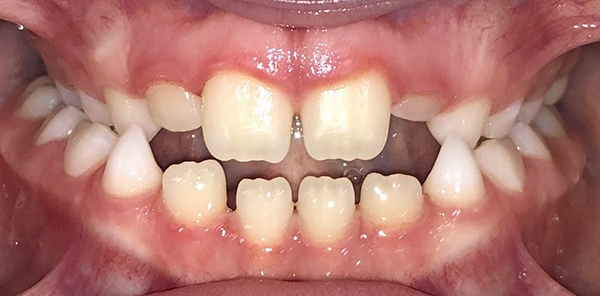

Actual Patient: Bailey

Img Before 3 1 Img After 3 1

Severe “Overbite”, BUCK TEETH, Narrow Jaws, Severe Deep Bite

Bailey Before 1 Beliy after img

Treatment Time:

7.5 months

Front View

Top View

Right & Left Sides